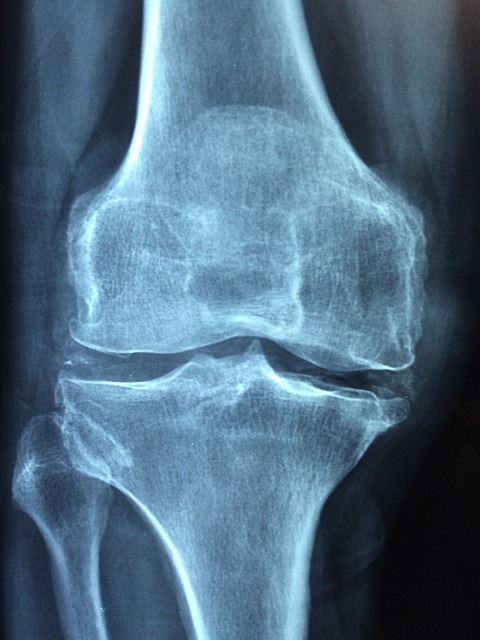

- 뼈와 관절에 영향을 미치는 문제. 여기에는 부러진 뼈(골절) , 관절 탈구, 감염 및 관절염이 포함될 수 있습니다.